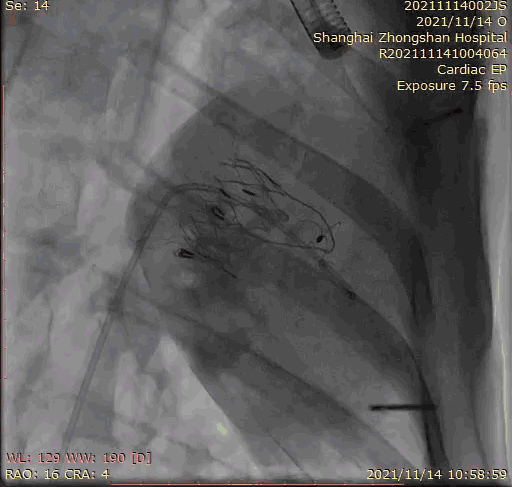

上海中山醫院葛均波院士、錢菊英院長、周達新教授、潘文志教授、潘翠珍教授、李偉教授共同完成此次臨床前研究。術后葛均波院士對Lux-Valve Plus的器械操作性能給予了高度評價,DSA和超聲影像也顯示出在本次研究中Lux-Valve Plus的安全性和有效性俱佳。

本次臨床前研究經右側頸靜脈置入LuX-Valve Plus輸送系統可調彎鞘管,在DSA及超聲引導下將人工三尖瓣瓣膜植入到原有三尖瓣位置,利用獨特的錨定技術將人工瓣膜支架可靠固定在預定的位置。